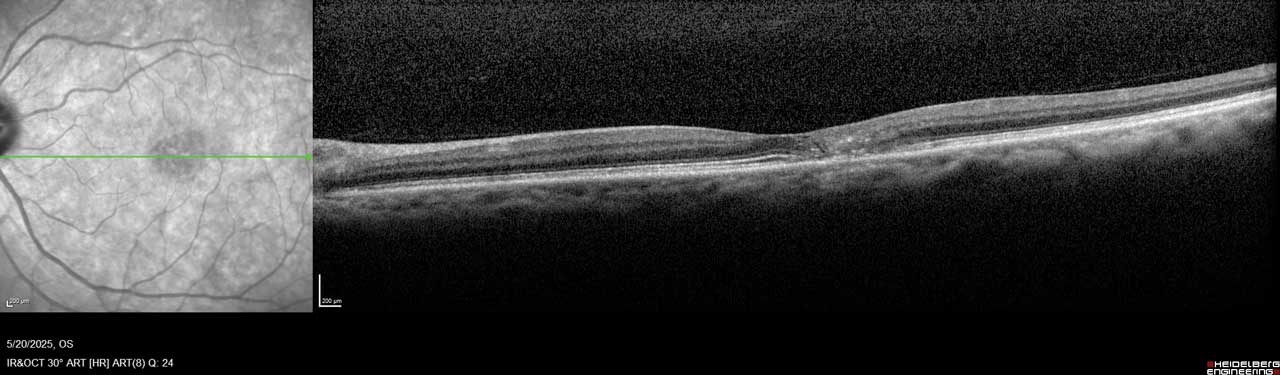

MacTel is believed to result from degeneration of Müller cells, the glial cells that surround and support neurons in the retina. This neurodegeneration leads to outer retinal atrophy and thinning, ultimately resulting in photoreceptor loss. In later stages, hyporeflective spaces in the outer retinal layer—most often within the foveal pit—can be observed on optical coherence tomography (OCT), indicating photoreceptor loss (Figure 1 and Figure 2).¹

Figure 2. Imaging of the left eye of this MacTel patient shows flattening of the temporal foveal pit, hyperreflective middle retina layers, and loss of outer retinal signals, including photoreceptors temporal to the center of the macula.